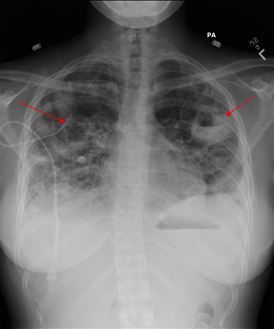

Fig 1. Chest x-ray shows cavitary lesions in both lung fields.

Laboratory evaluation showed WBC of 28,000/cm3 with left shift and thrombocytopenia. Results of rapid strep and mono spot tests were negative and blood cultures were drawn. Initial chest x-ray showed multifocal nodular infiltrates suspicious for septic emboli (Figure 1, click to enlarge). She was admitted to ICU for presumed sepsis and was treated with vancomycin and piperacillin-sulbactam (Zosyn).